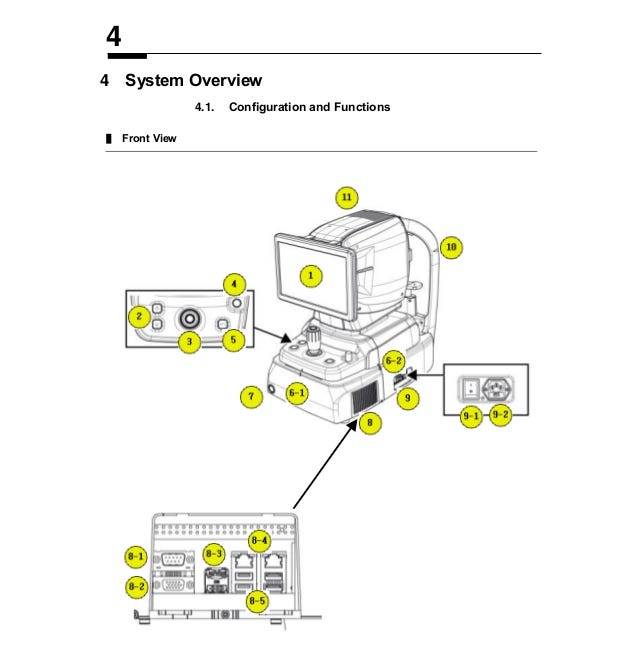

Bonus — Optical Coherence Tomography

Open Source Intelligence is not about knowing everything but about finding proper information and acquainted it as fast as possible to use it for specific purpose.

When you have no idea about device/software or any other finding, you should always depend on documentation that can be easily found from different sources.

It’s machine for optical coherence tomography and according to official site: Provides High-speed Scan, High-quality Image by using Huvitz’s outstanding optical technology and innovative image software. Shows extensive information, such as 3D structure of Retina, Macula’s thickness and separation, in a vivid image.

http://www.huvitz.com/oph_eng/product/HOCT-1.html

If you don’t know how to use this device or what kind of information it may contain, you need to find a manual guide.

It includes everything that you need to know about the device — from safety precautions, system overview or troubleshooting. Some of the manuals contains default password and installation guide as well.